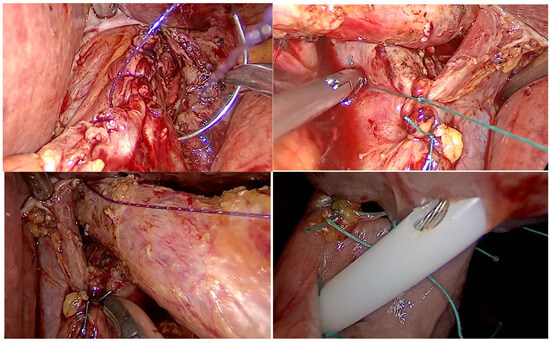

In an era where patient-reported outcomes have become more important, one of the tools that every surgeon should have in their bag is diagnostic laparoscopy. This versatile instrument can serve as a diagnostic confirmation and definitive treatment. Through a couple of trocars placed into the abdomen, a surgeon can diagnose a variety of surgical ailments, such as bowel infarction, the site of obstruction in bowel obstruction, occult hernias, and, last but not least, trauma. In addition, the oncological field is another place where it shines: intraperitoneal tumors, peritoneal carcinomatosis, and superficial liver metastases that were not identified upon imaging. Staging laparoscopy is recommended for pancreatic and gastric cancers, thus providing a potential indication for radical surgery. Laparoscopy is not only diagnostic, but after identifying the nature of the surgical disease one can perform various laparoscopic surgeries with net advantages when compared to the open approach.